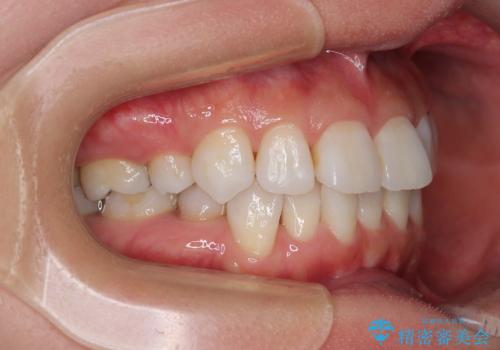

- 上下前歯の後戻りを気にして来院された患者様です。

インビザラインでの治療を希望されていて、デコボコの程度が中等度であり、安価なパッケージにて対応可能と判断されたため、インビザライン・モデレートを用いて矯正治療を行うこととしました。

インビザライン・モデレートは、製作できるアライナーの枚数に制限があるため、移動可能な量に限りがあるものの、インビザライン・ライトよりも枚数が多いため、幅広い症例に対応可能です。